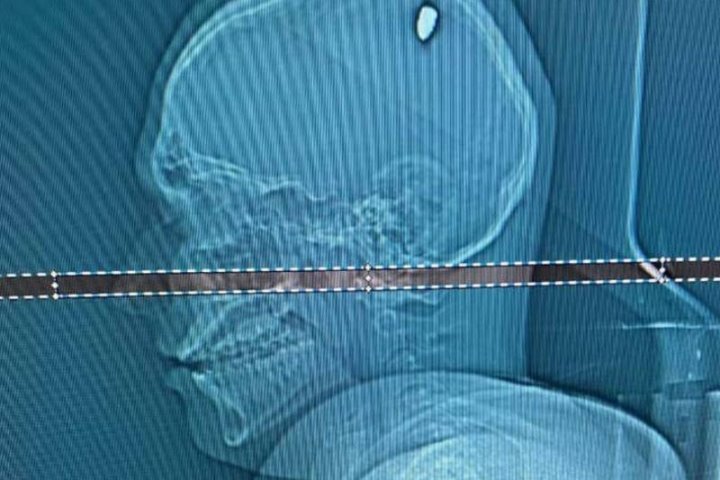

После сна левая рука Матеуса заметно ослабла — он не мог поднять даже легкие вещи. Парень обратился к врачу, и ему сделали МРТ.

На томографии выяснилось, что источником проблемы была пуля, застрявшая в одной из некритичных частей мозга. Ее извлекли хирургическим путем. Операция прошла успешно, и Матеус уже находится на пути к полному выздоровлению.